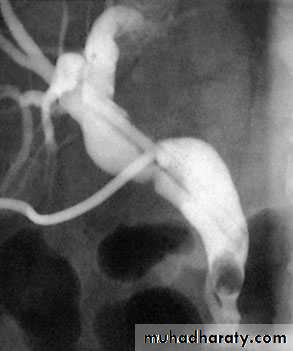

53Transhepatic cholangiogram showing a stricture of thecommon hepatic duct

Al-Madena copy